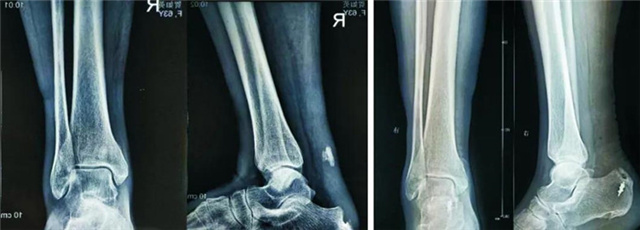

患者贺xx,女,64岁。主因绊倒致右足跟疼痛、行走无力2月余入院。2月前绊倒致右足跟部疼痛、肿胀,自行休养约1周后疼痛、肿胀消退。行走时自觉右足无力感,上坡时明显。当地医院B超检查提示跟腱连续性中断。门诊以跟腱陈旧性断裂收入。40年前有类风湿性关节炎病史,高血压病史20年。检查:右足跟及跟腱部无肿胀,无压痛,跟腱腱性部中央可触及空虚感,提踵试验阳性,Thompson征阳性。X线片:踝关节无异常,跟骨骨刺,踝关节后方皮下有一不规则高密度影。入院诊断:右跟腱陈旧性断裂。入院第3日在腰硬联合麻醉下行右跟腱陈旧性断裂修复术。取跟腱内侧切口,术中见跟骨结节撕脱骨折,骨折块约2.5cm×1.5cm,与跟腱一起回缩4.5cm。术中证实为跟骨结节撕脱骨折。钝性分离粘连跟腱,足跖屈位复位跟骨结节撕脱骨块,克氏针临时固定,锚钉拧入跟骨内,锚钉线缝合固定撕脱骨块和跟腱。

1.跟骨骨折约占全身骨折的1.2%,跟骨后结节撕脱骨折占跟骨骨折的1%-3%。发病率很低,临床经验少,易误诊及漏诊。

2.阅片不仔细,受跟骨骨刺干扰,未能认识跟骨后结节撕脱骨折,误认为是陈旧性跟腱断裂形成的钙化。

3. 提踵试验阳性、Thompson征阳性为跟腱断裂的诊断依据,本例撕脱骨块回缩4.5cm,类似跟腱断裂,导致误诊。